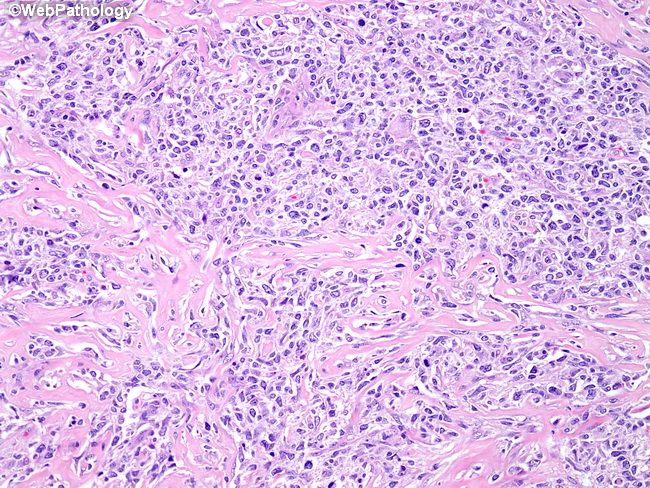

Патолоджи аутлайн

Патолоджи аутлайн 113 фото